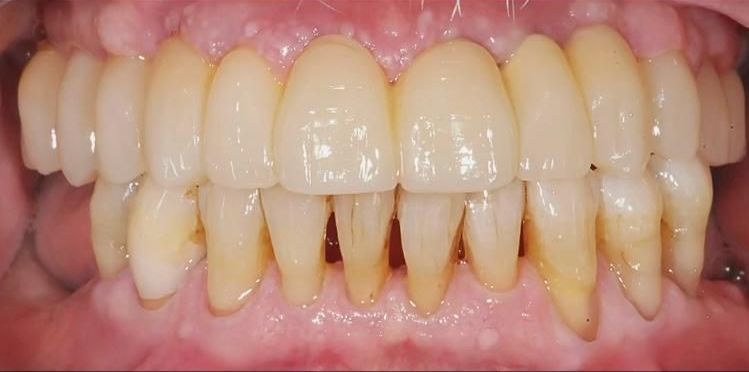

Nel nostro studio effettuiamo la chirurgia implantare con la tecnica del carico immediato guidata; essa si avvale di un software che pianifica l’intervento, lo attua in modo poco invasivo in tempi rapidi con un decorso post-operatorio non invalidante e privo di fastidiosi postumi.

Con la tecnica del carico immediato avremo quindi una riabilitazione funzionale ed estetica in un’unica seduta. Impieghiamo materiali e impianti sicuri, di altissima qualità e a fine intervento ti sarà consegnato un passaporto che garantisce il lavoro svolto a livello internazionale e identifica esattamente il tipo di impianto utilizzato, in caso di bisogno anche all’estero.

Il nostro paziente arriva in Studio e tra anestesia, preparazione del campo operatorio e intervento vanno via un paio di ore.

Dopodiché applichiamo il provvisorio ma spesso procediamo con la protesi definitiva, la cui preparazione richiede un paio di giorni. Quella del carico immediato in Chirurgia Guidata è una tecnica che abbatte tempi e costi oltre che ridurre l’invasività della chirurgia tradizionale.